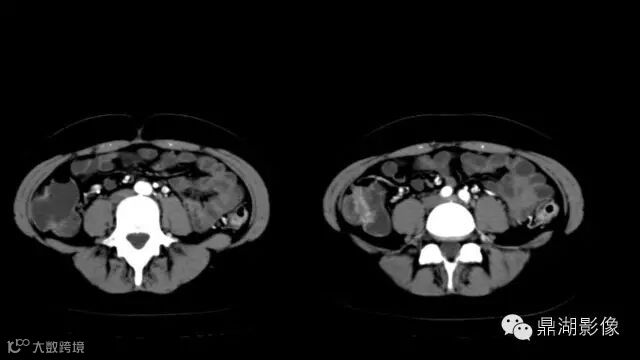

what's the meaning of fat halo sign?

粘膜下水肿或脂肪沉积,可致肠壁内呈低密度层(halo征),其最初用来描述溃疡性结肠炎,是良性肠道病变的结果,无特异性,也可存在于放射性肠炎,移植-受体疾病和慢性缺血性肠炎以及单性的肥胖症患者。

Fat halo aslo can be seen in normal terminal ileum.

It is the comb sign the most specific sign for crohn's disease.